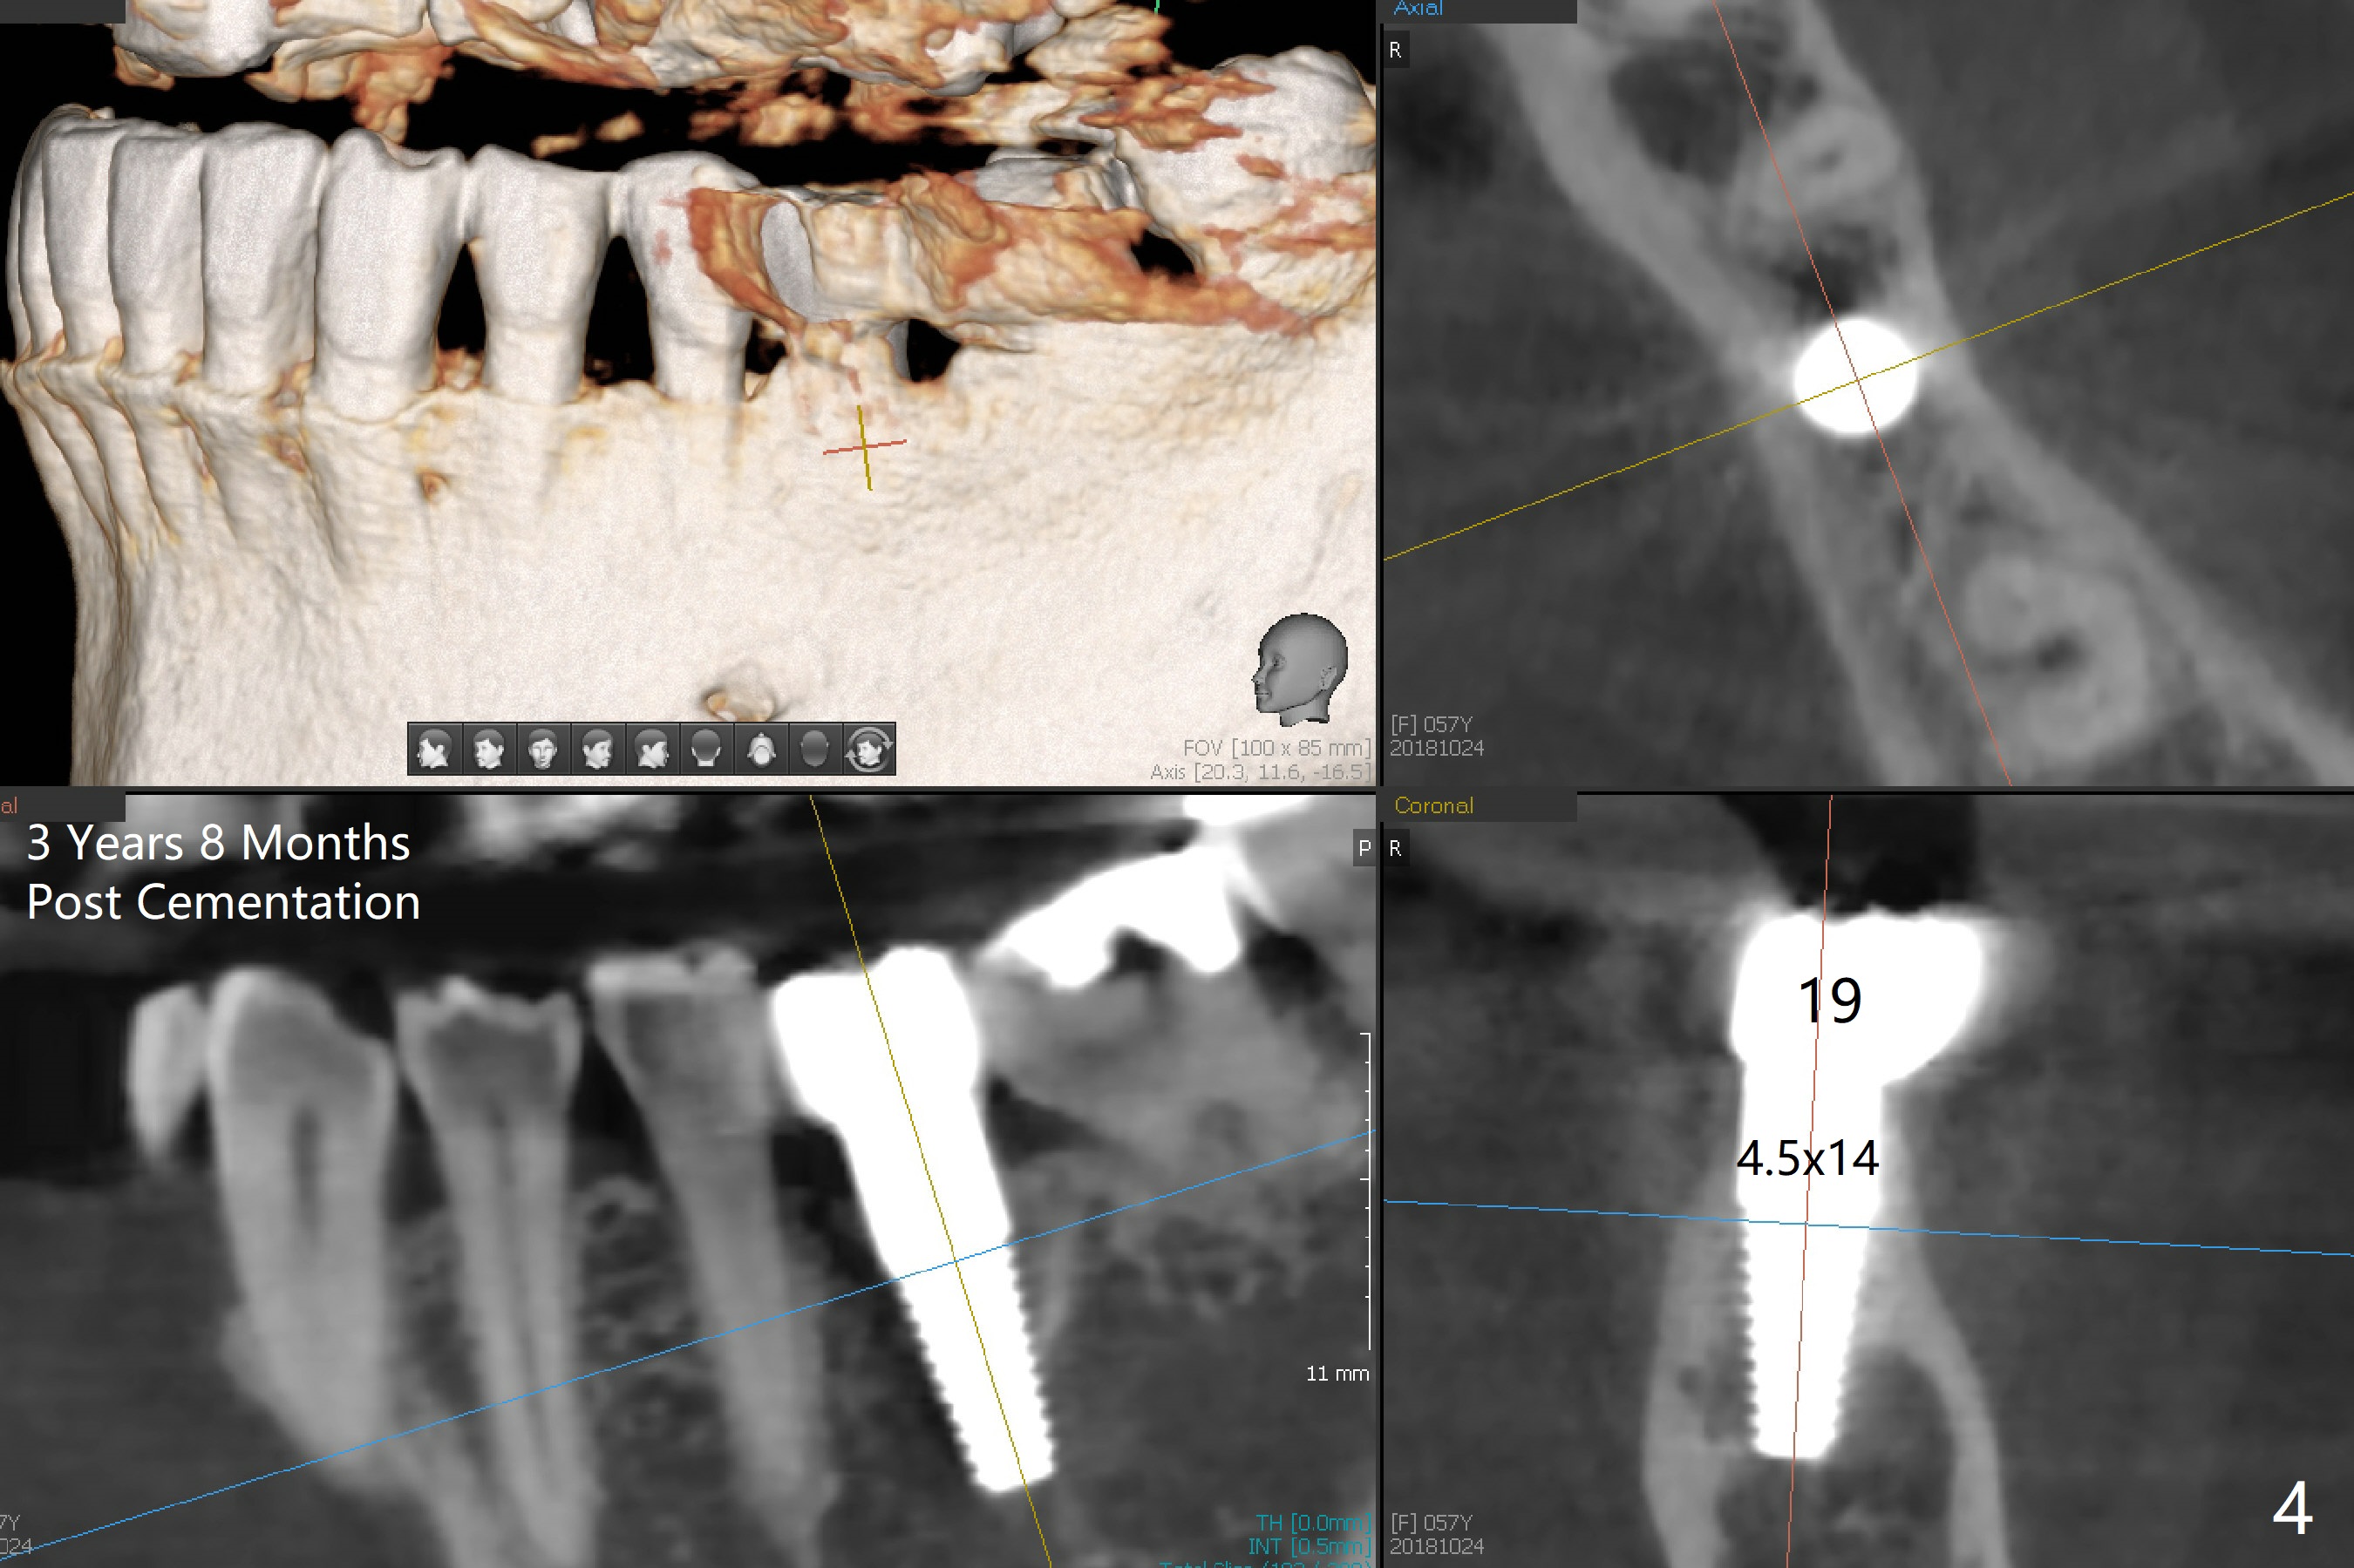

A 57-year-old woman returns with pain in the upper right quadrant (Fig.1,2). In fact the mesiobuccal root of the tooth #2 has vertical fracture. Although the socket destruction at #3 is not as extensive as that of #2, the socket of #3 has communication with the sinus. Prior to socket preservation, a piece of Osteogen plug is inserted at #3. PRF should be prepared for severe bone loss. In contrast there is no bone loss around the implants at #19 or #30 (Fig.1,3,4). Although the socket at #2 is slightly open 9 days postop, bone graft appears to be present (Fig.5). The bone at #2 and 3 seems to regenerate 7 months post socket preservation (Fig.6). Three short implants seem to be better than 2 implants for 3-unit FPD (Fig.7-9).